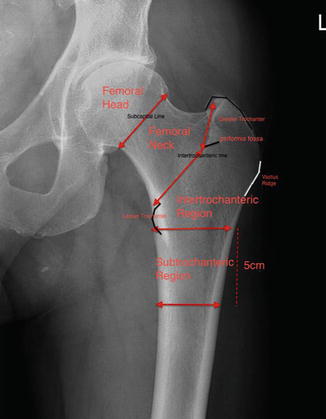

Relevant anatomy of proximal humerus. Histologically, each kidney is composed of approximately 1 the renal tubule continues from bowman's capsule and consists of the following parts: Anatomy of the femoral neck and head, with comparative data from caucasians and hong kong toogood, p.a., skalak, a. From the proedify teas anatomy study guide, this is part 1 of the lesson on anatomical terminology.